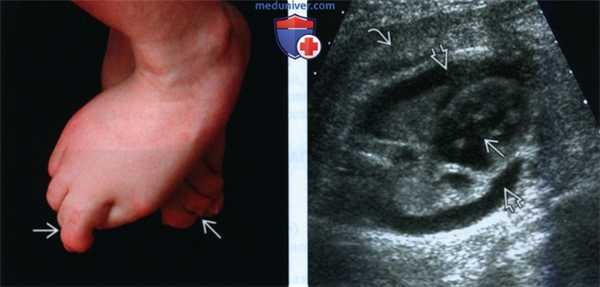

(Слева) Типичная Y-образная синдактилия II-III пальцев у молодого человека с ССЛО. Положение стопы свидетельствует об отсутствии ответа на тактильную стимуляцию, что характерно для ССЛО.

(Справа) УЗИ грудной клетки плода с тяжелой формой ССЛО, поперечная плоскость. Визуализируются двусторонний плевральный выпот и значительное утолщение кожи. Отмечается артериовенозный дефект перегородки. Аутопсия показала однодольное строение легких.